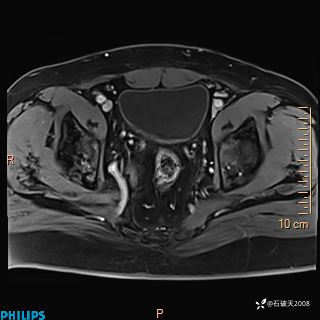

2023年3月份MRI影像

增强轴位